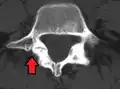

-

Anterolisthesis L5/S1 -

Anterolisthesis L5/S1. Blue arrow normal pars interarticularis. Red arrow is a break in pars interarticularis. -

Anterolisthesis L5/S1